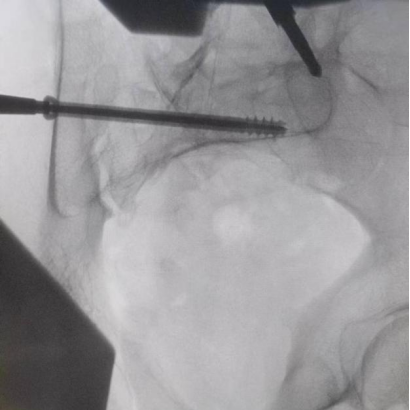

圖為透視下見置入的骶髂螺釘,位置、長度精準(zhǔn),無絲毫偏差